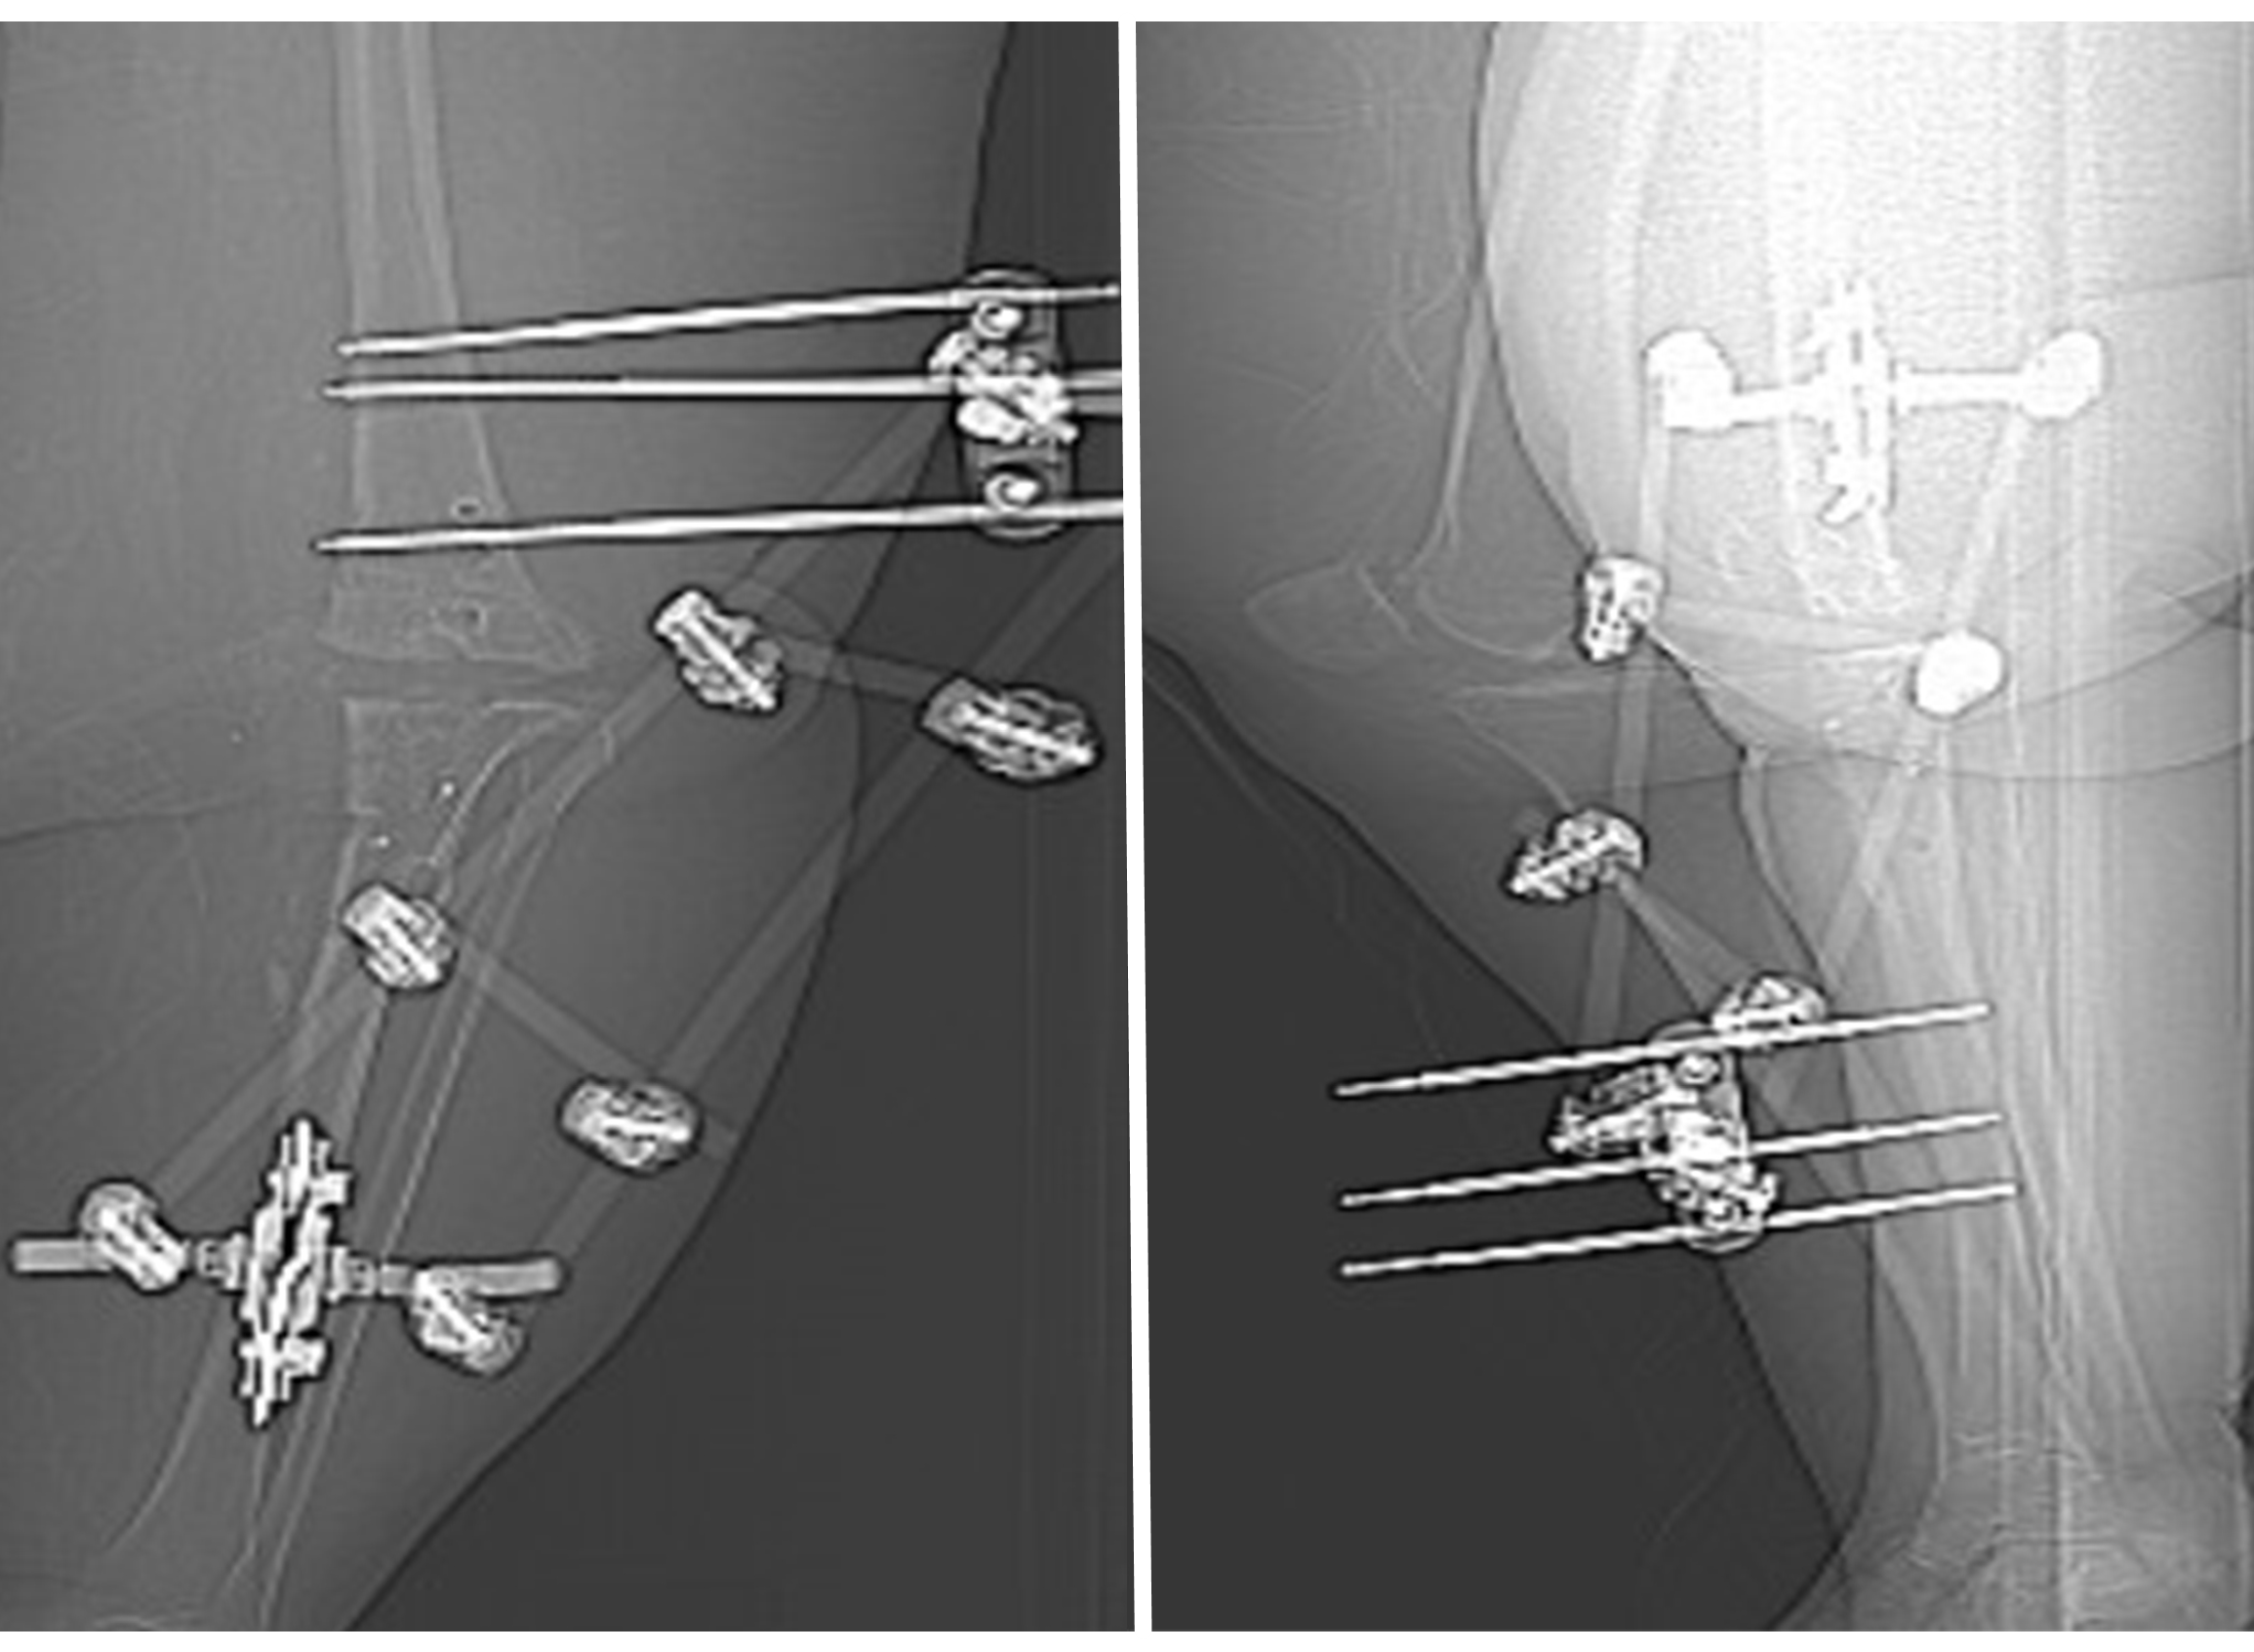

A doctor reviews scan of knee with a patient

These scans of the patient's knee from the front (left) and side views show the hardware from previous surgeries that needed to be removed before the knee fusion surgery with a customized implant could be done.

To begin, we removed the failed prosthetic, plates, and screws from past surgeries. While this is a normal part of revision joint surgery, this patient’s surgery was more complicated and took two to three times longer due to the volume of tissue we had to work through to access the joint and hardware.

During the procedure, we placed slow-releasing antibiotic beads near an infection discovered in the patient’s knee. We also installed an external fixator device to provide more stability for her leg during the waiting period while her custom knee implant was designed.